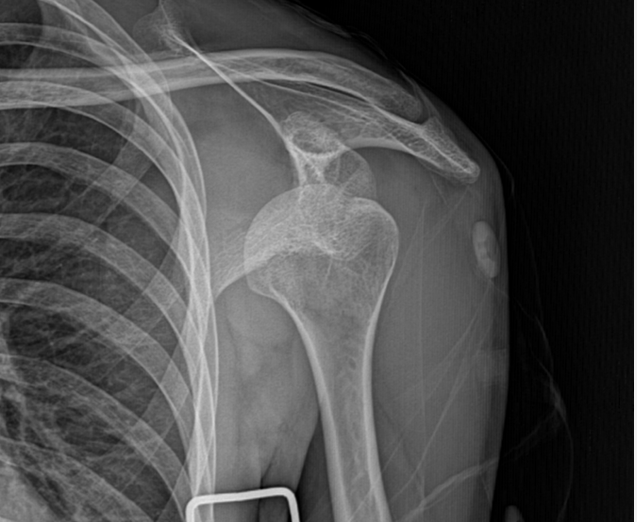

Shoulder Fracture

어깨골절

어깨골절은 상완골, 쇄골, 견갑골 등 어깨관절을 구성하는

뼈가 부러지는 것을 말합니다.

스포츠 활동 증가로 어깨골절 발생도 증가하고 있으며,

골다공증이 있는 경우에는 가벼운 충격에도

골절이 쉽게 발생할 수 있어 주의가 필요합니다.

대표적인 어깨골절

상완골 골절

상완골 골절은 어깨에서 팔꿈치까지 이르는 긴 팔뼈인 상완골이 부러진 상태입니다.

골절의 발생 위치에 따라 크게 세 가지로 분류됩니다.